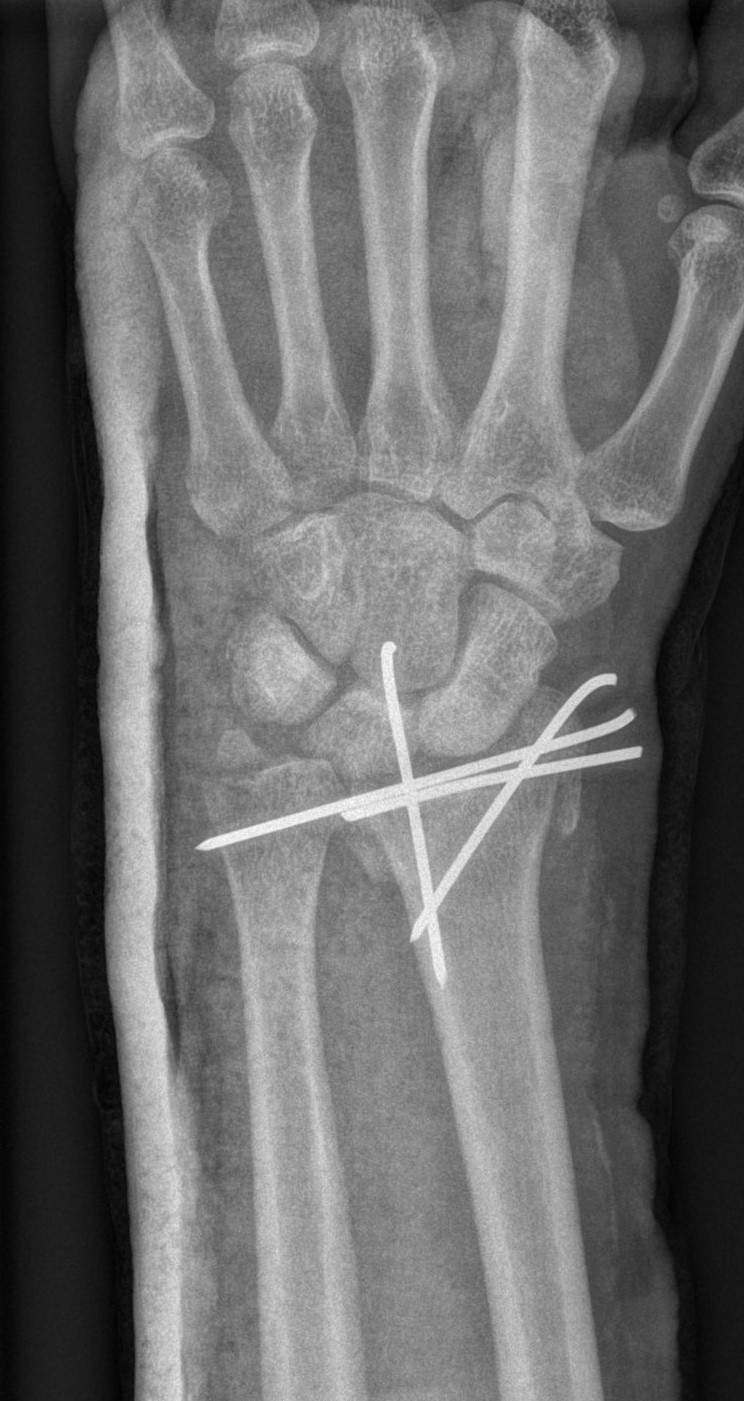

Successful surgery to reduce and fixate with the plate of neglected, displaced fracture of the distal radius

Treatment of neglected, displaced or united distal radial fractures (DRFs) is difficult, because it requires either wedging the almost consolidated fracture and reduction to the correct position, or cutting the united bone and putting it in the correct position (corrective osteotomy). Both treatments are associated with the risk of failure and complications. The paper presents a case of almost fully united DRF in a man, in whom 5 weeks after the injury, and after unsuccessful primary fixation with K-wires, the bone fragments were surgically wedged, aligned and fixed with a palmar plate. The result of treatment after 2 months was satisfactory. Early surgery allowed for a significant shortening of the recovery period and allowed the patient to return to work.